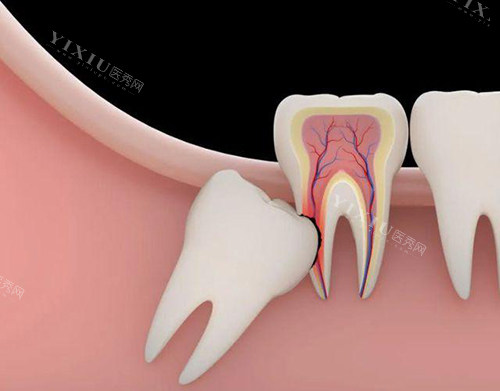

在哈尔滨,拔智齿是很多人会遇到的口腔问题。智齿带来的困扰可不小,有时候疼起来真是让人坐立不安。要是你正在考虑拔智齿,哈尔滨远东口腔医院值得你了解一下。

医生团队经验充足,擅长处理各种复杂的智齿情况。医院引进了智能化口腔扫描仪,能够定位智齿的位置,减少手术创伤。而且,他们的小创口拔牙技术也非常成熟,切口小,改善比较快。对于一些复杂的情况,比如需要使用超声骨刀去骨的阻生智齿拔除,医院也能提供特色的服务。